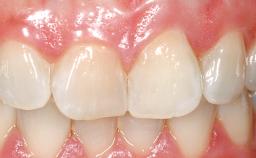

This 43-year-old male patient, a non-smoker, came to our practice because of a fracture of tooth 12 caused by a bicycle accident. Due to the combined para- and infrabony crown and root fracture, tooth extraction, and subsequent implant placement were suggested to the patient as the therapy of choice. The patient had high esthetic expectations with regard to the treatment outcome and asked for an immediate fixed provisional restoration. His individual esthetic risk profile summed up to a medium esthetic risk.

Immediate Flapless Placement of an Implant in a Maxillary Right Lateral Incisor Site